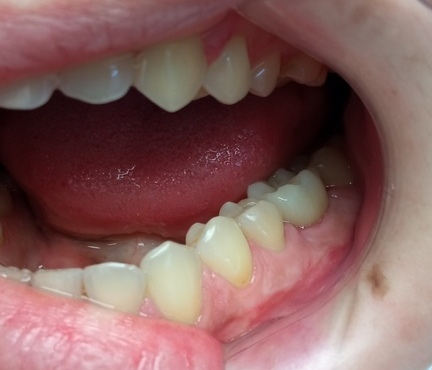

- В ходе осмотра состояние полости рта было хорошее, зубы рядом с отсутствующим были сохранены и не поражены кариесом.

- Пациента очень волновало, чтобы зуб не отличался от соседних.

У 1 варианта большой минус – обточка здоровых соседних зубов, но дешевле и быстрее. Мостовидный протез служит 5-7 лет.

2 вариант дольше и дороже, но надежнее и навсегда. Во время лечения отсутствующий зуб будет закрыт временной коронкой.

Взвесив все «за» и «против» пациент выбрал вариант 2 – надежность.